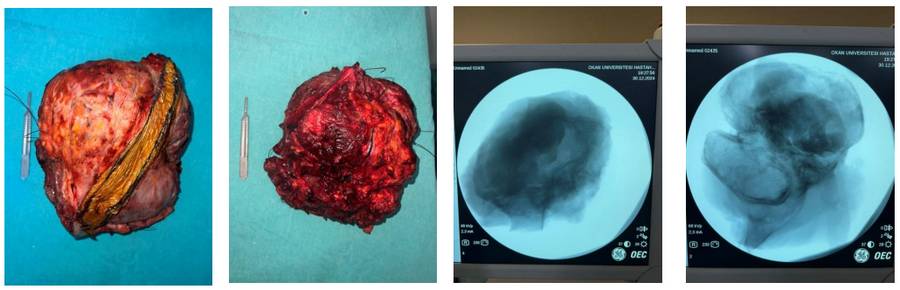

Ameliyat Esnası: Çıkarılan tümör dokusunun klinik ve skopi görüntüsü